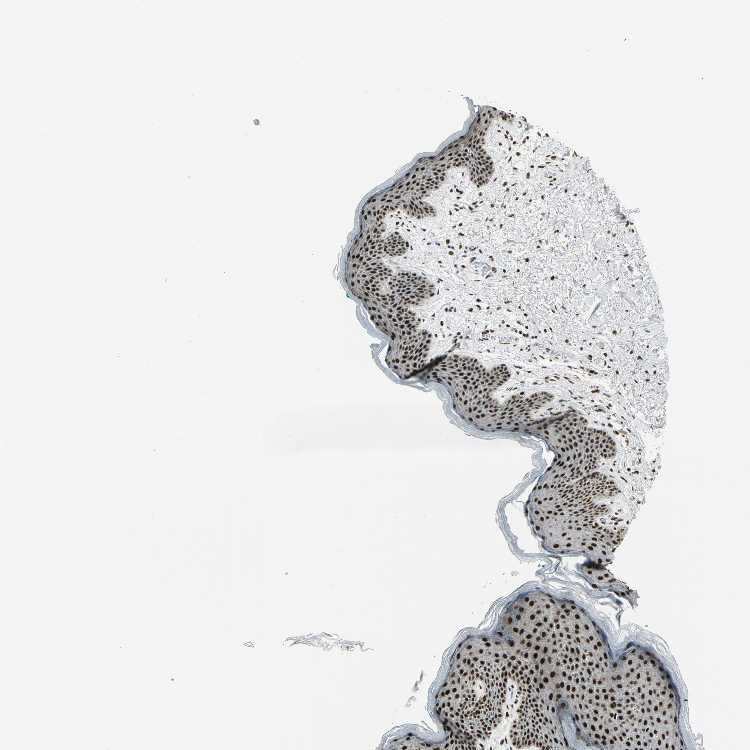

SKIN 1 - Antibody stainingi

Antibody staining in the annotated cell types in the current human tissue is reported as not detected, low, medium, or high, based on conventional immunohistochemistry profiling in selected tissues. This score is based on the combination of the staining intensity and fraction of stained cells.

Each image is clickable and will lead to virtual microscopy that enables deeper exploration of all samples and also displays staining intensity scores, fraction scores and subcellular localization as well as patient and tissue information for each sample.

Antibody CAB004208

Langerhans High

Fibroblasts Medium

Keratinocytes High

Melanocytes Medium

SKIN 2 - Antibody stainingi

Epidermal cells High